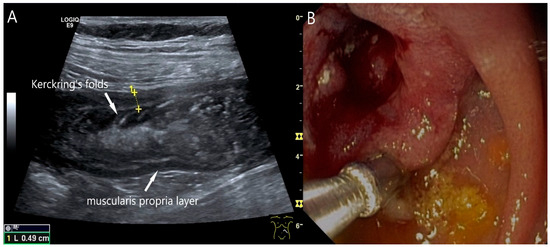

Small intestine metastasis of pleural mesothelioma. Hypoechoic tumorous wall thickening (T) between the markers. The normal wall with Kerckring’s folds (KF) is visible adjacent to it. Next to the small intestine is a round hypoechoic tumor-suspicious lymph node (L).

Figure 22.

Jejunal wall hematoma with a Quick ratio <5%. Smoothly defined, distinct wall thickening and lumen obstruction. The wall stratification is indistinct, slightly hyperechoic, and clearly blurred and unfocused (a). The Kerckring folds are thickened and also very blurred (b).